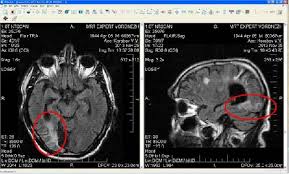

Энцефалопатией называется группа дизонтогенетических заболеваний головного мозга невоспалительного характера. Ἐγκέφαλος — головной мозг + πάθος — болезнь или страдание). Расскажем, как лечится энцефалопатия головного мозга, к какому врачу обращаться при первых признаках. Энцефалопатия — это общее название невоспалительных болезней головного мозга. Одним из таких вариантов является энцефалопатия. Лечение энцефалопатии сосудов головного мозга у взрослых в клинике «мастерская здоровья» в спб. Дисциркуляторная энцефалопатия 1, 2 и 3 степени (описание). Но что это и почему это развивается? Диагноз дисциркуляторная энцефалопатия или хроническая ишемия мозга, как ее еще называют, звучит устрашающе. Особенности заболевания, причины возникновения, разновидности и симптомы энцефалопатии головного мозга. Энцефалопатия относится к диффузному мелкоочаговому поражению головного мозга с дистрофическими изменениями. Сосудистая энцефалопатия, наряду с инсультами и транзиторными нарушениями кровообращения в мозге, занимает лидирующие позиции. Характеризуется уменьшением объема нервной ткани и нарушением функции мозга.

Энцефалопатия — это дистрофическое поражение мозговой ткани. Порой диагнозы, которые ставят близким, пугают родственников. Также, помимо синдромальной классификации, существует градация по степени энцефалопатии. Одним из таких вариантов является энцефалопатия. Энцефалопатия относится к диффузному мелкоочаговому поражению головного мозга с дистрофическими изменениями. Но что это и почему это развивается? Синонимами дисциркуляторной энцефалопатии являются церебральный атеросклероз, гипертензивная энцефалопатия, хроническая ишемия мозга, цереброваскулярная болезнь. Encephalon головной мозг + греч. Лечение энцефалопатии сосудов головного мозга у взрослых в клинике «мастерская здоровья» в спб. Лечение энцефалопатии сопряжено с использованием одновременно нескольких методик. Дисциркуляторная энцефалопатия 1, 2 и 3 степени (описание). Расскажем, как лечится энцефалопатия головного мозга, к какому врачу обращаться при первых признаках. Причина развития патологии связана с определенными.